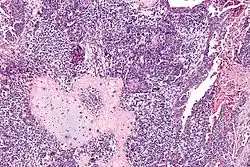

![]() صورة مجهرية of a carcinosarcoma. صبغة الهيماتوكسيلين واليوزين. صورة مجهرية of a carcinosarcoma. صبغة الهيماتوكسيلين واليوزين. | |